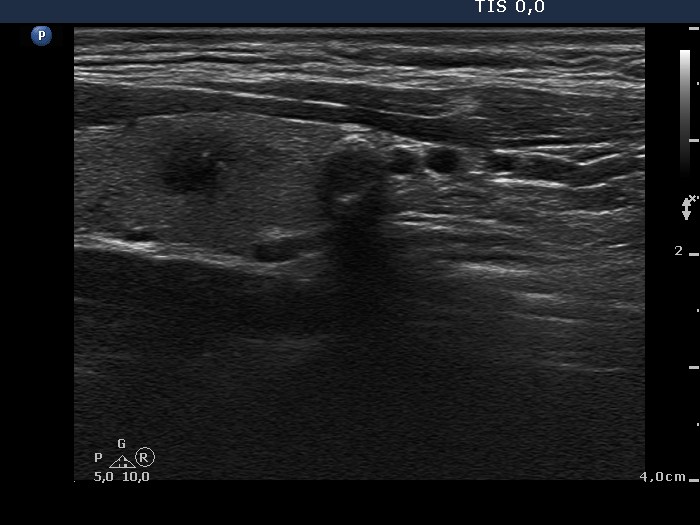

100 consecutive cases of papillary cancer - case 034 (ultrasonographic picture 6)

Left lobe, another longitudinal scan.